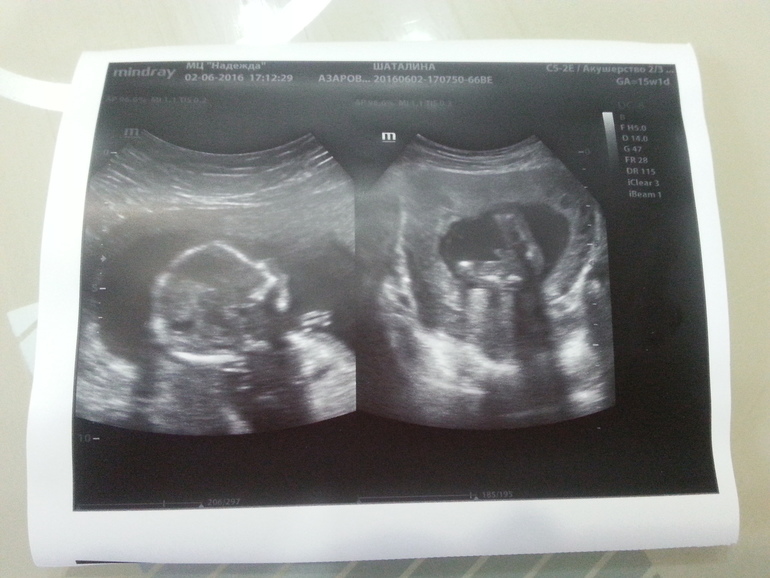

Фото пузиковИ так, девочки! Сегодня в 17.00 тайна была раскрыта и мы узнали пол нашего второго малыша!

У нас будет второй сыночек!!!

Ходили на УЗИ все вместе. Я, муж и сынуля, и конечно пузожитель) Сыночек вел себя хорошо, с интересом смотрел на экран и показывал пальчиком все время на братика

Кстати, сыночек все время сосал пальчик, пока на него смотрели

И узистка сказала, что красивый профиль у него)

А теперь фото моего животика с утра и конечно доказательство, что мы мальчики)